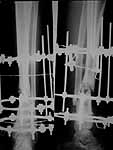

The case was presented in the Russian ortho list. A male 27 years old sustained an open (GA-II) fracture of the tibial shaft. Plating was performed on admission. Early deep infection developed, so the plate was removed and a small wire Ilizarov ex-fix applied. A sinus persisted about 6 month, after removal of a small fragment soft tissues got closed. All seemed to be healing, but on x-ray prior expected hardware removal in Dec 2004 a nonunion was seen (attached). Wire tracts now look quiet. The patient walks with a cane. He is tired with 1.5 year of ex-fix and requests to do something.